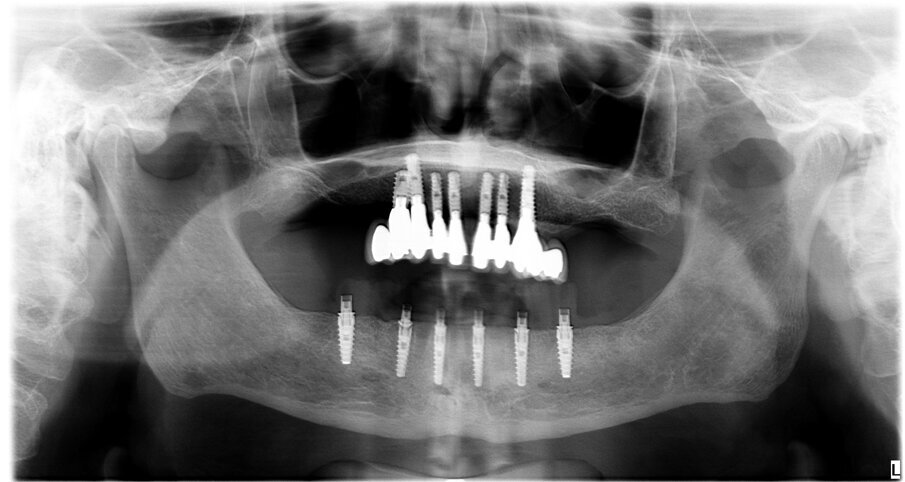

Paziente di sesso maschile di 73 anni, con anamnesi negativa per patologie di rilievo. All’esame clinico e radiografico si evidenzia nell’arcata inferiore la presenza di residui radicolari a supporto di un vecchio ponte, con attacchi per la stabilizzazione di una protesi scheletrata di tipo mobile. Prima di procedere alla fase chirurgica e di rimuovere lo scheletrito viene eseguita un impronta digitale con scanner (3Shape) in modo da registrare la dimensione verticale che verrà utilizzata come riferimento per la realizzazione del carico immediato. In sedazione cosciente e previa terapia antibiotica si procede alla rimozione dei residui radicolari, quindi si esegue una generosa osteotomia e si procede al posizionamento di numero 6 impianti assiali (AB Dental device) a esagono interno. Si esegue quindi la sutura dei lembi con vicryl 4/0 e si procede alla prese dell’impronta digitale utilizzando gli scan body come transfer (Figg. 1-11). I file in STL vengono inviati al laboratorio per la realizzazione della protesi provvisoria a carico immediato. Si applicano quindi le viti di guarigione. Dopo 72 ore si procede alla consegna del provvisorio che rimarrà in bocca per 4 mesi in attesa dell’osteointegrazione (Figg. 12-23).

Fig. 23 - Rx con carico immediato.